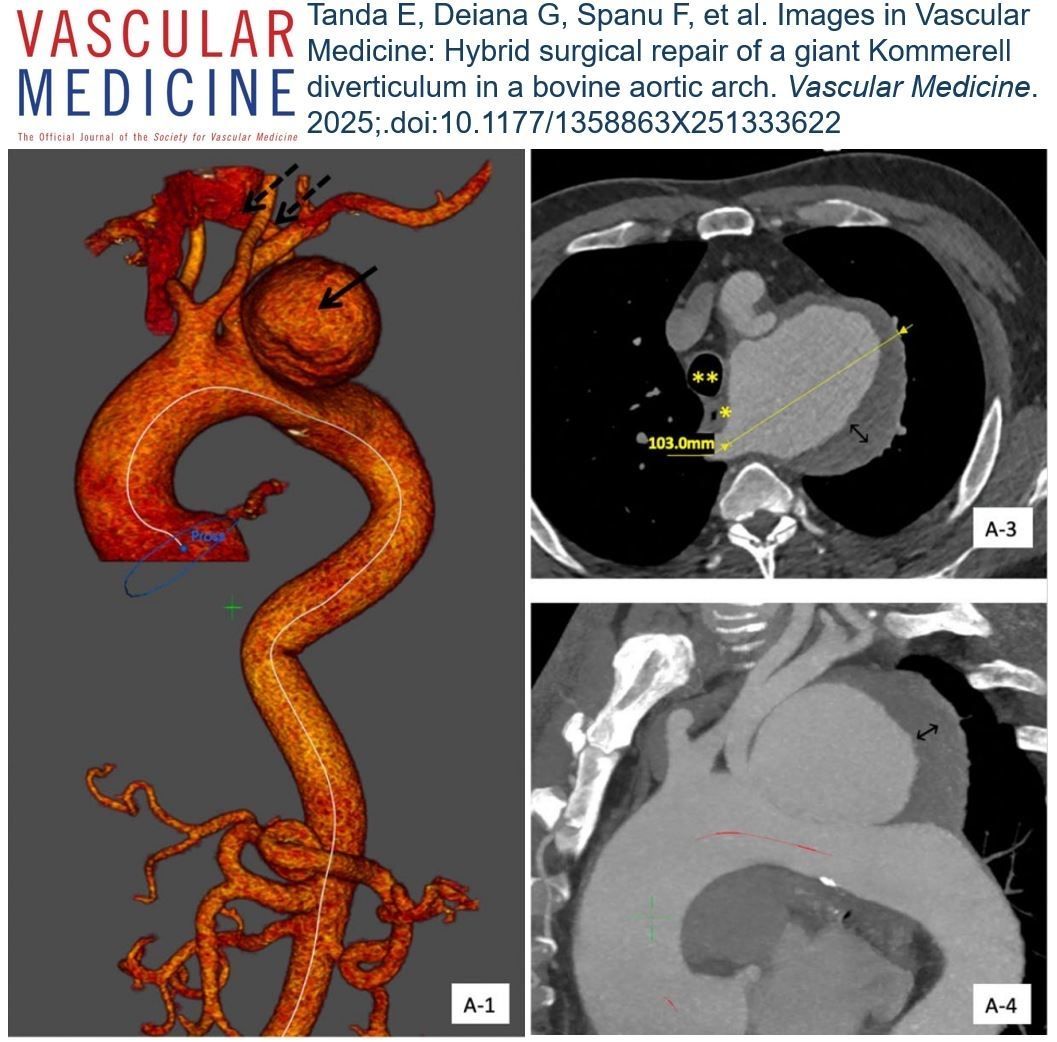

Online First! In these #ImagesInVascMed, Prountzos and colleagues describe a rare aortocaval fistula between a persistent left superior vena cava and the aorta at the site of prior endovascular repair. #Aneurysm #Aorta

https://t.co/7w09YZk3PJ